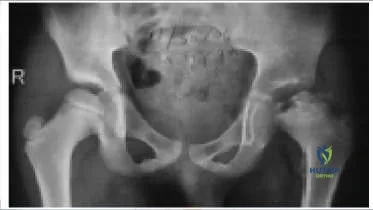

Which of the following accurately describes this radiograph (Slide):

According to Herringâ s classification, this radiograph demonstrates a lateral pillar C because the lateral pillar is collapsed by more than 50%.